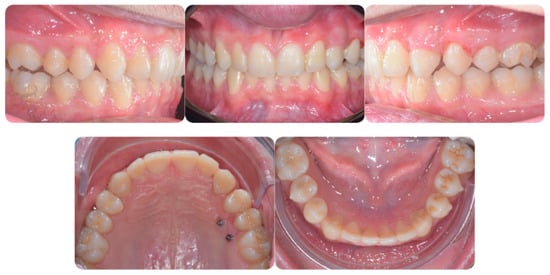

Figure 2 panoramic and CBCT showing the moderate palatal 2.3 impaction. Lateral X-rays confirming a Class I skeletal and dental malocclusion with deep bite.

Figure 2.

Cephalometric analysis, panoramic and CBCT of the first patient. Lateral X-rays confirming a Class I skeletal and dental malocclusion with deep bite.